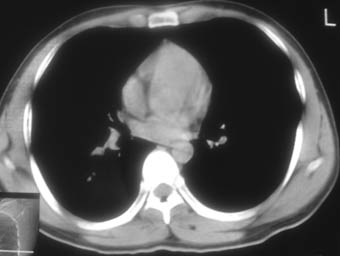

锁骨骨折复查,发现肺内高密度影,行ct检查。

男性,35岁,无任何感觉,无明显发热感冒病史。

纵隔窗!

右肺下叶背段斑片状阴影,边缘模糊,纵隔内未见肿大淋巴结,病人无发热及感冒史,要考虑浸润型肺结核,可结合ppd检查,或短期抗炎治疗复查。

右肺下叶背段长椭圆型病灶,边缘较规则,无明显分叶征、毛刺,远段未见阻塞征象,病灶较松散,纵隔窗明显小于肺窗,年龄35岁,支气管稍示变窄,纵隔内未见明显肿大淋巴结,这些都不支持肿瘤。病人无任何感觉,无明显发热感冒病史,首先考虑结核(也是结核好发部位),慢性炎症不能完全除外。